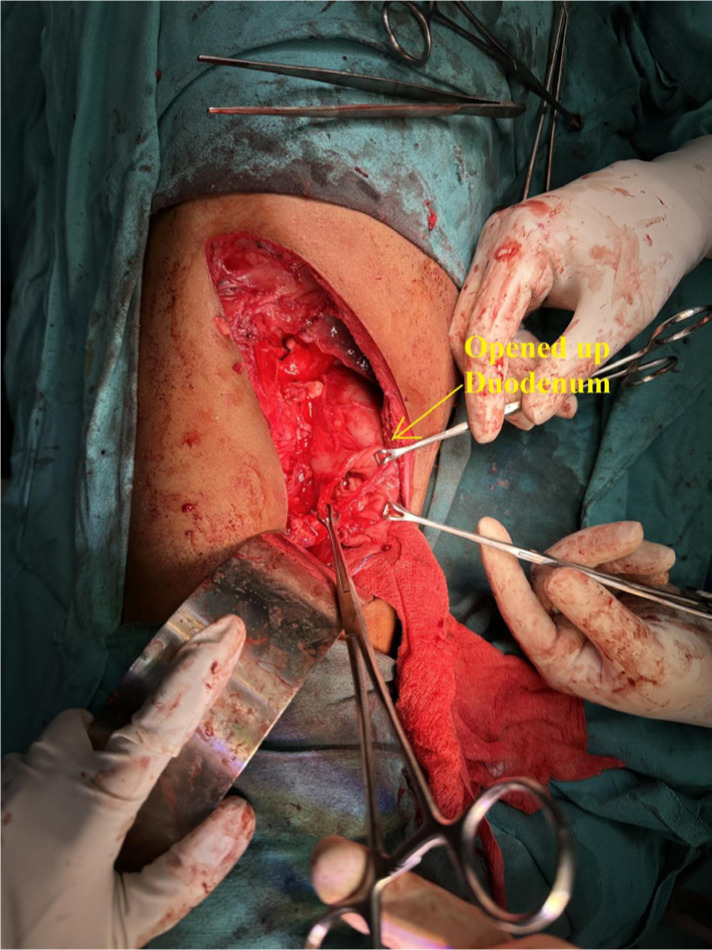

Examination of both testes revealed normal findings. Abdominal and pelvic computed tomography (CT) scan revealed a deformed right kidney with soft tissue mass of size 11 × 7 × 6.5 cm in the mid and lower pole extending to the hilar region, with compression of pelvicalyceal system and an upper pole calculus of size 2.4 × 1.2 cm (Figure 1). Post contrast examination showed inhomogenous enhancement of the mass with no evidence of contrast excretion from the kidney. The CT of his chest showed no nodules or pulmonary metastases. The patient underwent a right open radical nephrectomy with lymph node dissection. Intraoperative, a 15 × 7 cm right renal mass was noted infiltrating the psoas muscle, duodenum, and liver. Additionally, a few enlarged retroperitoneal lymph nodes were also noted. The procedure involved the excision of the infiltrated mass in the duodenum with subsequent repair of the duodenum and the creation of feeding jejunostomy and retrograde duodenostomy (Figure 2). The histopathology report indicated a high-grade malignant NSGCT. Additionally, the submitted lymph nodes tested negative for malignancy. Immunohistochemistry performed showed diffuse positivity in the tumor cells for OCT-3/4 of moderate to strong intensity; patchy cytoplasmic granular staining for alpha-fetoprotein (AFP) was noted mostly in the solid areas—focal cytoplasmic granular positivity for alpha-methylacyl-CoA racemase (AMACR) and focal membranous positivity for CD10—and were negative for PAX-8, CD117, GATA-3, Vimentin, and CD30 (Figures 3 and 4). There was no loss of expression of INI-1; focal incomplete membranous staining for CK-7 and CK-20 was noted in the papillary areas (Figure 5).

Figure 2: Intraoperative picture. Suggestive of opened up duodenum after radical nephrectomy.